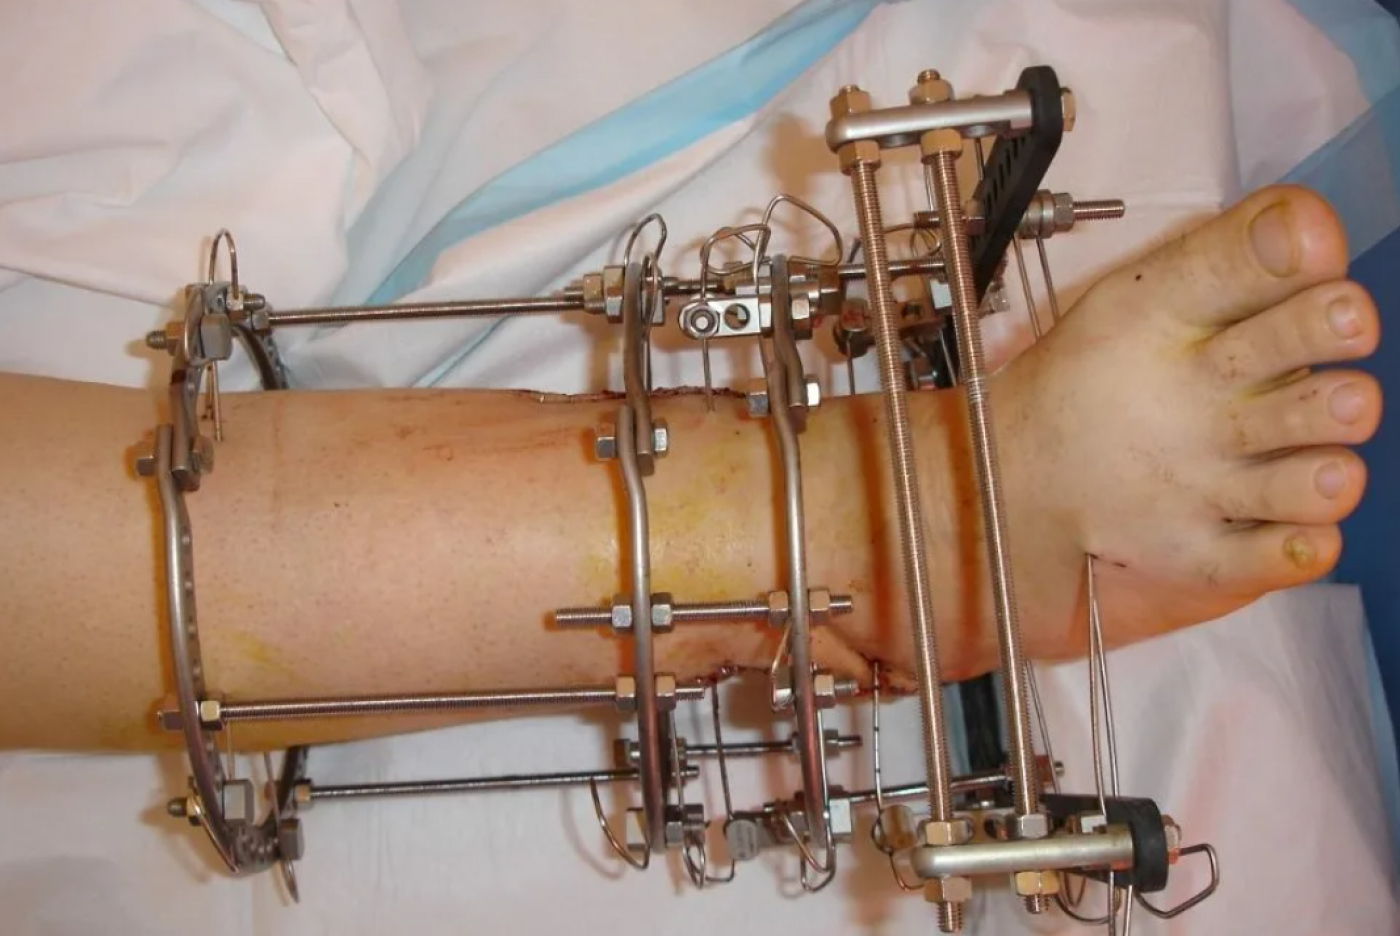

Аппарат Илизарова: принцип работы и применение